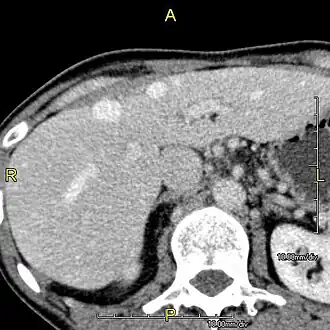

Disease

Left lobe liver tumor

The liver is a vital organ and supports almost every other organ in the body. Because of its strategic location and multidimensional functions, the liver is prone to many diseases.[58] The bare area of the liver is a site that is vulnerable to the passing of infection from the abdominal cavity to the thoracic cavity. Liver diseases may be diagnosed by liver function tests–blood tests that can identify various markers. For example, acute-phase reactants are produced by the liver in response to injury or inflammation.

After resection of left lobe liver tumor

Liver transplantation is the only option for those with irreversible liver failure. Most transplants are done for chronic liver diseases leading to cirrhosis, such as chronic hepatitis C, alcoholism, and autoimmune hepatitis. Less commonly, liver transplantation is done for fulminant hepatic failure, in which liver failure occurs rapidly over a period of days or weeks.